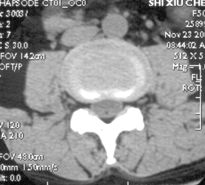

CT

CT可清楚地显示椎管横断面的骨性结构,对侧隐窝狭窄,黄韧带肥厚,椎间小关节病变及神经孔周围极外型椎间盘突出的显示有独特的临床价值,CT可提出比椎管造影更准确的鉴别诊断。CT对蛛网膜下腔观察不如脊髓造影。